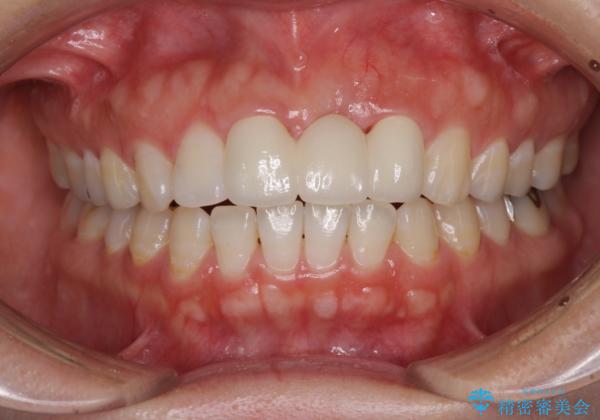

前歯のブリッジが気に入らない 歯肉移植術を併用した前歯のブリッジ

- 接着タイプの前歯のブリッジが不自然であるとのことで来院された患者様です。

欠損部の歯肉が窪んでいるため、歯肉移植により形態を改善し、オールセラミックブリッジにて補綴することとしました。